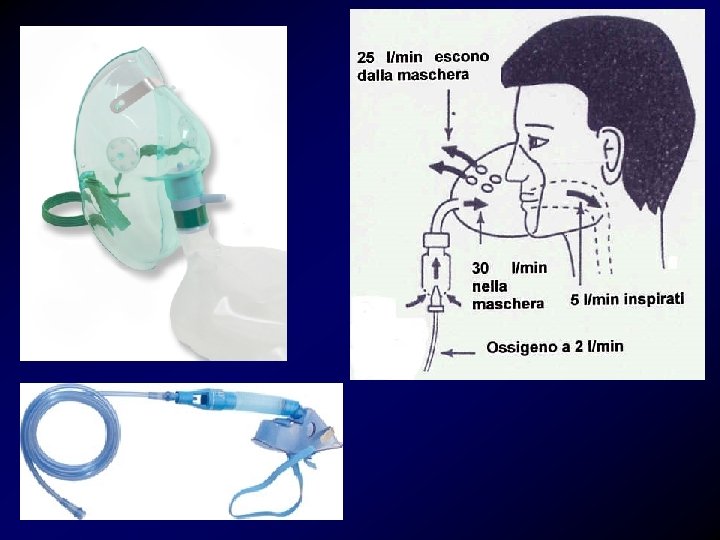

LINEE GUIDA PER IL TRATTAMENTO DELLA TEP • Maschera facciale con sistema Venturi per erogare alte frazioni inspiratorie di ossigeno. • Morfina per alleviare i dolori toracici, la dispnea e la grave apprensione del paziente. Controindicata se la PAS < 100 mm. Hg. • Bicarbonati e. v. nell'acidosi metabolica grave (p. H < 7. 1). • Antibiotici nell'infarto polmonare come profilassi di una possibile infezione della zona necrotica. • Eparina sodica, somministrata precocemente nel sospetto di TEP in attesa della conferma diagnostica per prevenire l' estensione dei trombi e proteggere il paziente dalle recidive di embolia.

Tecnicamente questa maschera fornisce una percentuale nota di O 2 all'interno della maschera purché sia erogato il flusso indicato sul beccuccio di ingresso della M. VENTURI (v. foto di esempio: il flusso di 8 Lt x min fornisce una concentrazione di O 2 all'uscita del 40 %). Le maschere hanno un volume che varia da 100 a 300 ml e sono in grado di somministrare una Fi. O 2 dal 24% al 60% con flussi tra i 6 e i 10 L/min.